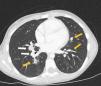

At diagnosis she was asymptomatic, with normal physical examination and a positive tuberculin skin test (induration of 13mm). Left hilar enlarged lymph nodes were suspected on her chest-X-ray and bilateral enlarged mediastinal and hilar lymph nodes with bilateral lung nodules were detected on chest computed tomography (CT) (Fig. 1). Serial gastric aspirate specimens for acid-fast bacilli smear microscopy, PCR and mycobacterial culture were negative in the patient; however, M. tuberculosis cultures were positive in both her father and four-year old brother, with isolates showing resistance to isoniazid, rifampicin, pyrazinamide, ethionamide and streptomycin. These findings were sufficient for the diagnosis of MDR pulmonary TB, reserving the bronchoscopy in the event that the patient did not have a known TB contact or antimicrobial sensitivity pattern. Therefore, an injectable-free treatment regimen was initiated with levofloxacin (18.5mg/kg/day), linezolid (14mg/kg/day), clofazimine (100mg every second day), cycloserine (18.5mg/kg/day) and ethambutol (18.5mg/kg/day).